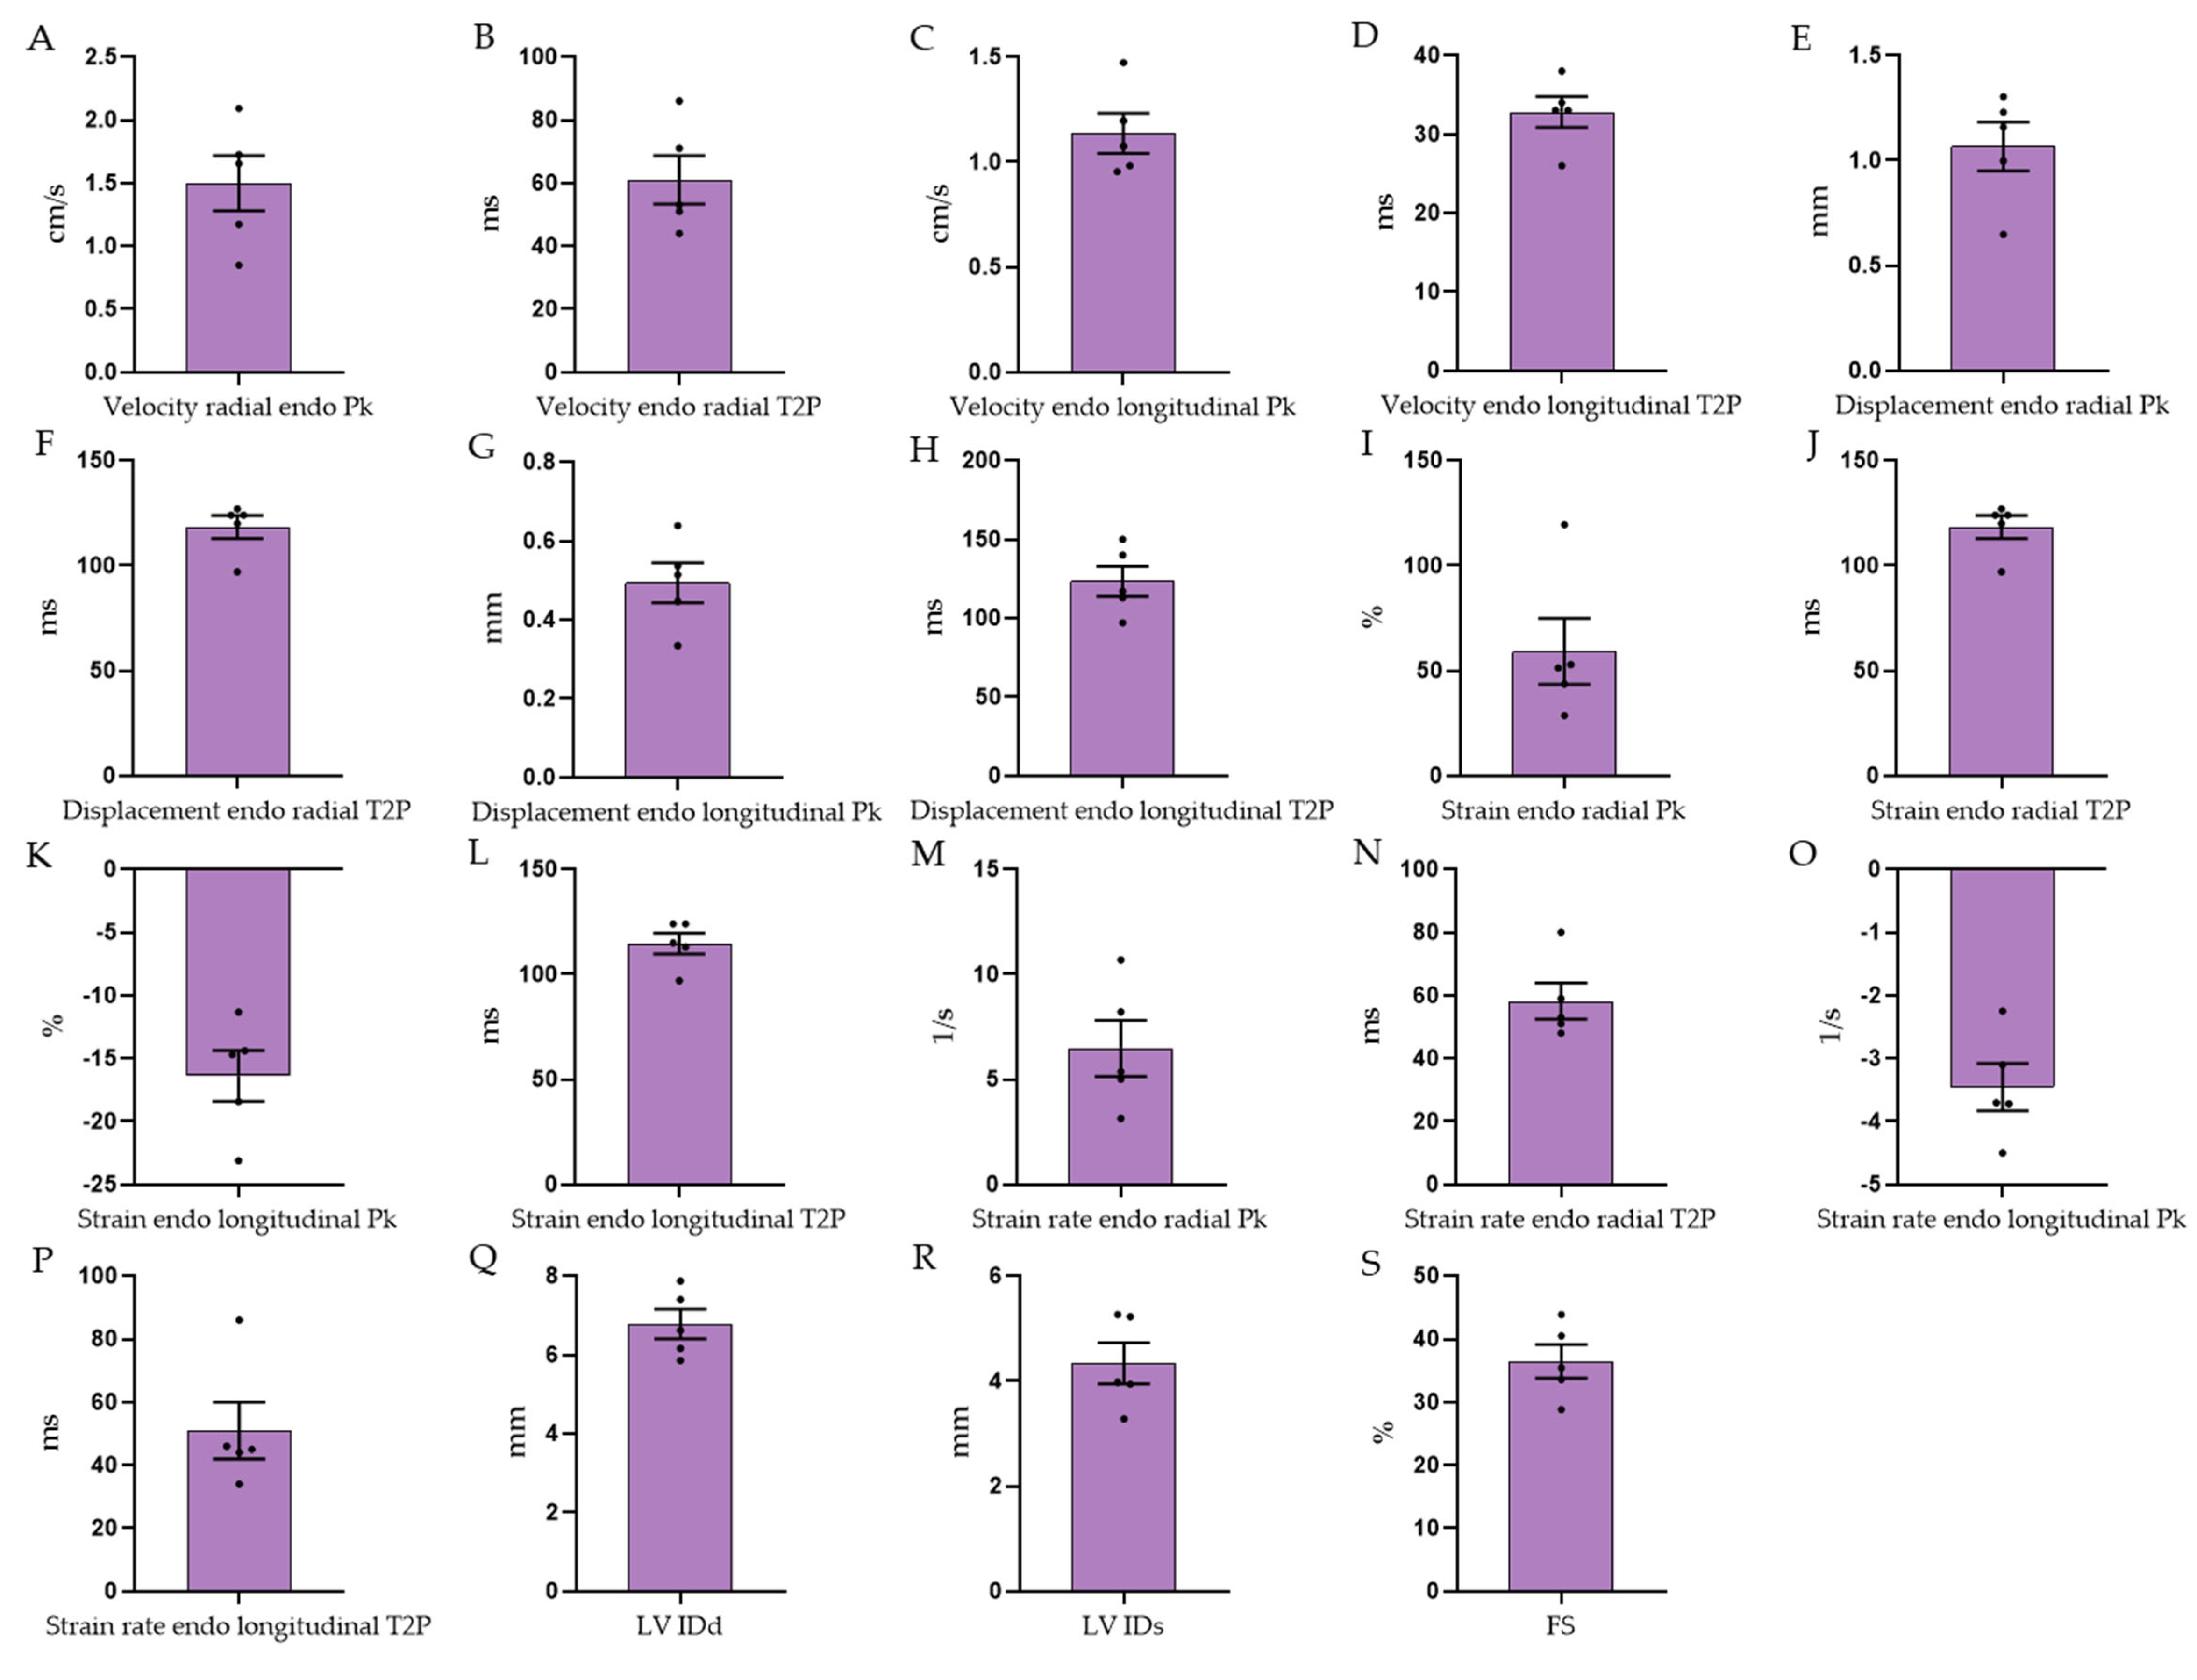

3.3. Echocardiographic Measurements